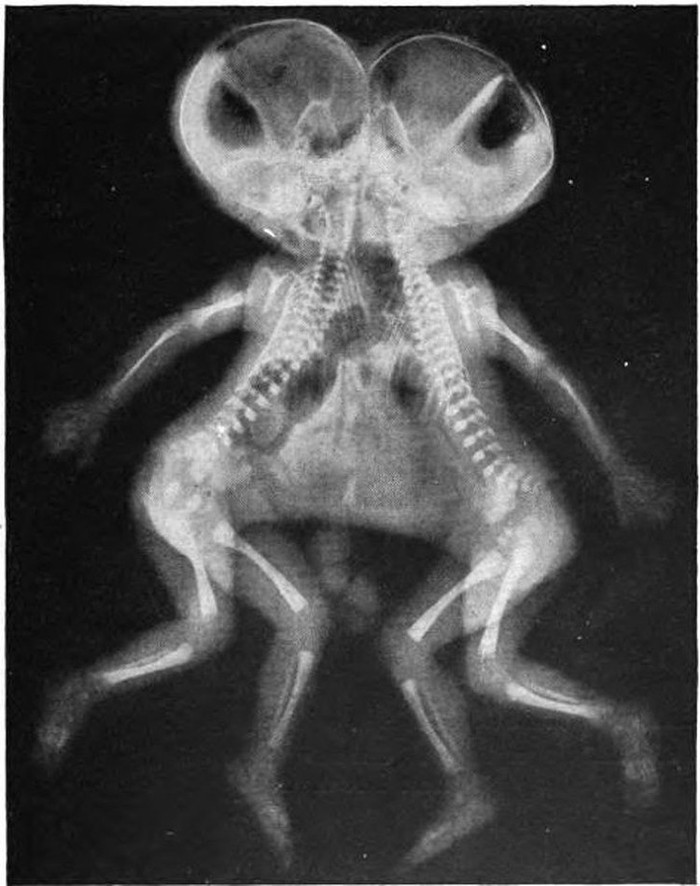

Seperti ini bayi kembar yang dempet. (Foto: Brightside)